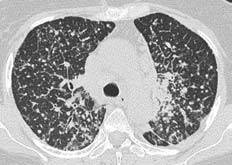

Чтобы человек несведущий смог разобраться в результатах КТ, следует знать о нюансах чтения снимков. Рассмотрим самые актуальные:

- Очаговые образования представляют собой участки белого цвета на черном фоне (на снимке-негативе). В реальности пораженная область, скорее всего, имеет более темный цвет, чем здоровые ткани легкого.

- Если врач заметит на снимке участки кальцинирования или обызвествления (капсул, пропитанных солями кальция) вокруг очага, это может быть признаком доброкачественности образования. Кальцинаты по цвету похожи на кости скелета, видимые на этом снимке. Такие явления часто обнаруживаются после затяжных простудных заболеваний, бронхитов или уже излечененного туберкулеза и представляют собой некий шрам на легких. Пациента с образованием, на котором заметны признаки кальцината, пульмонологи обычно просят раз в полгода делать контрольные снимки.

- В случае, когда образование представляет собой так называемое «облачко» или очаг по типу «матового стекла», требуется более предметное обследование. Внешне оно выглядит как затуманенная область с размытыми границами. В ряде стран пациентам с такими образованиями сразу рекомендуется операция, даже если оно не растет. Уже доказано, что в 80% случаев такие очаги являются предраковым состоянием легких. Альтернатива немедленной операции — постоянное наблюдение с контрольными снимками раз в полгода-год.

Очаговые изменения

Очаговые изменения в лёгких могут быть разного размера. Очаги мелкого диаметра 1-10 мм выявляются при различных диффузных патологиях лёгочной ткани. Очаги с высокой плотностью и довольно чётки краями в основном наблюдаются в интерстиции лёгкого. Различные очаги низкой плотности, напоминающие матовое стекло, с нечёткими контурами возникают при патологических изменениях в респираторных отделах дыхательных органов.